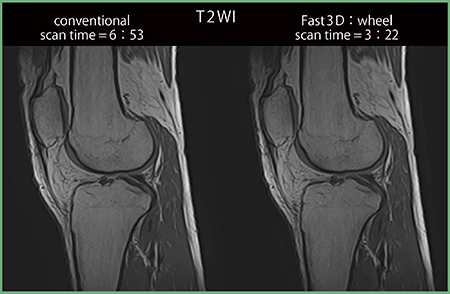

従来,3Dシーケンスは高分解撮像に適しており,また,撮像された3D画像からMPR画像を作成することにより任意断面での診断が可能になる。一方,3Dシーケンスは撮像時間が長く,拘束時間が長くなることにより患者への負担が増大する場合がある。

当社アプリケーションの一つである可変フロップアングル法を使用したMPV(multi planar voxel)対応シーケンスで“Fast3Dモード”を使用すると,図6に示すように,従来の1TR内で1 slice encode(SE)を収集する撮像方法と比較して,コントラストを維持しつつも従来の約半分の撮像時間で撮像することが可能となる4)。

MPV対応シーケンスのFast3Dモードは,1TR内でphase encode(PE)方向とSE方向とを混合して収集する高速撮像手法である。Fast3Dモードの収集法の一つであるwheel の場合,k-space中心からPEおよびSEをwheel状に収集する。Fast3D factorはk-spaceの実収集率を示し,残りはhalf Fourierにより補間される。

また,より高分解能の撮像を行う場合はSNRの低下は避けられないが,撮像時間短縮の代わりに加算回数を2倍にすることにより,同じ撮像時間でSNRを担保した画像を撮像することが可能である。

図6 従来手法とFast3Dモードのコントラスト比較